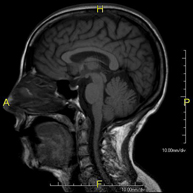

- RM Cerebral (craneal)

Prueba diagnóstica no invasiva que consiste en la obtención de imágenes de alta definición anatómica del cerebro mediante el empleo de un campo electromagnético y ondas de radio (con un emisor y un receptor). No utiliza radiación ionizante. Indicaciones: problemas vasculares, pérdida de memoria, epilepsia, cefalea, malformaciones, sospecha de tumor, meningitis.